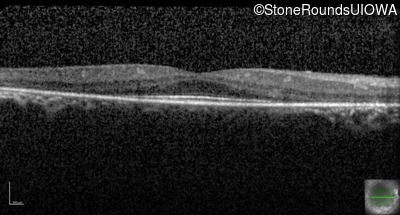

Optical Coherence Tomography - Right - 20/25

Exemplar / OCT Stack